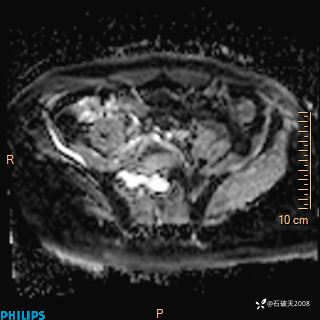

2023年3月份MRI影像

增强轴位